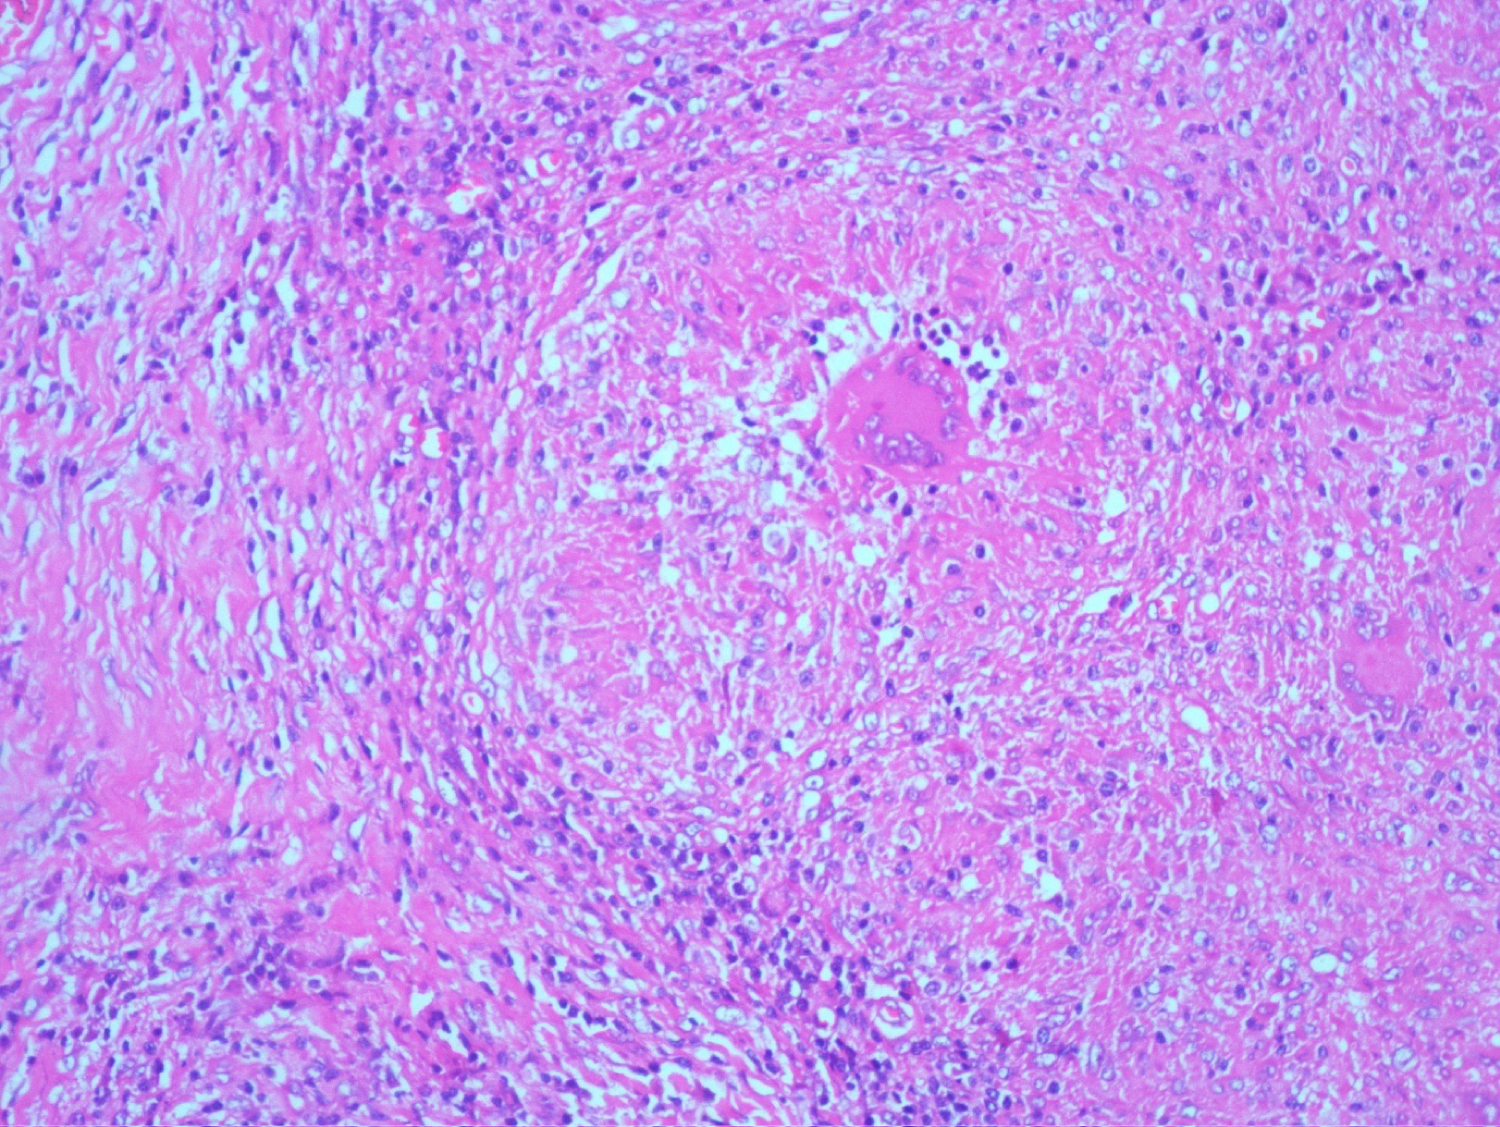

She was managed as a case of Tubercular Lymphadentits with ANCA mediated focal necrotising crescentic glomerulonephritis. She received alternate days of plasmapheresis with 0.4 L/Kg of plasma removed in each session, for a total duration of five sessions and Inj Methyl prednisolone of 500 mg for three days followed by oral prednisolone at 01 mg per kg body weight. Anti-tubercular therapy in the form of cap Rifampicin, Tab Isoniazid, Tab Ethambutol and Tab Pyrazinamide was initiated after her plasmapheresis sessions were finished. She was also treated with low monthly dose of injection Cyclophosphomide of 500 mg IV. There was rapid improvement in her clinical condition and urine output as a result of this regime. After two weeks post-initiation of plasmapheresis, her serum creatinine settled to 1.9 mg/dl. Her steroids were rapidly tapered in view of her active tuberculosis and low dose Inj Cyclophosphamide 500 mg IV, was continued every 02 weeks for three months; followed by maintenance therapy with tablet Azathiopyrine at 01.5 mg/Kg body weight. She had good response to her antitubercular regime and a repeat CT of the chest and abdomen at two months, revealed marked resolution of her lymph nodes in the retroperitoneal region and was shifted to the three drug maintenance regime and her Tab Pyrazinamide was stopped. At six months, follow up p-ANCA returned negative. She was continued on anti-tubercular therapy for nine months. She received maintenance therapy for her necrotic crescentic glomerulonephritis with Tab Azathiopyrine for a period of 24 months. Presently she is on regular follow-up and maintaining stable creatinine of 1.7 mg/dl with resolution of her Tubercular Lymphadenitis (Figure 1, Figure 2, Figure 3 and Figure 4).

Figure 2: Haematoxyline and Eosin (H&E) stain (low power view) effaced lymph node architecture with caseation necrosis. View Figure 2

Figure 3: Haematoxyline and Eosin (H&E) stain: Langerhan giant cells with caseation necrosis. View Figure 3